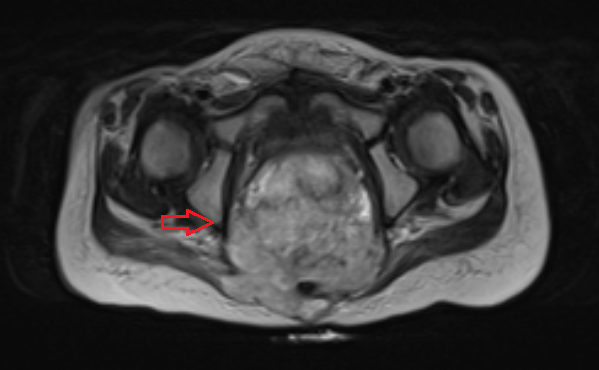

Компьютерная томография органов грудной клетки, брюшной полости, малого таза используются для оценки распространения опухолевого процесса (рис.5).

Рисунок 8. КТ органов брюшной полости - на снимках вы можете увидеть опухоль яичника.